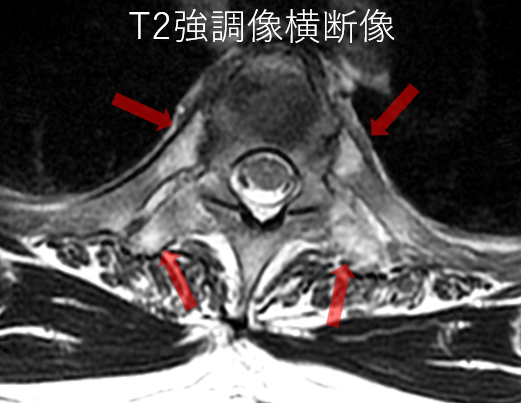

- 【椎体の後方成分にも注目】

脊椎炎では、椎体の変化だけではなく、肋椎関節、椎間関節や棘突起にも炎症が起きる。

- 【脊椎関節炎(SpA)での肩関節病変】

腱板炎、大結節(腱付着部)のエロージョン、付着部の骨髄浮腫が特異的所見である。

関節包周囲軟部組織の浮腫および造影効果は関節リウマチより高度である。